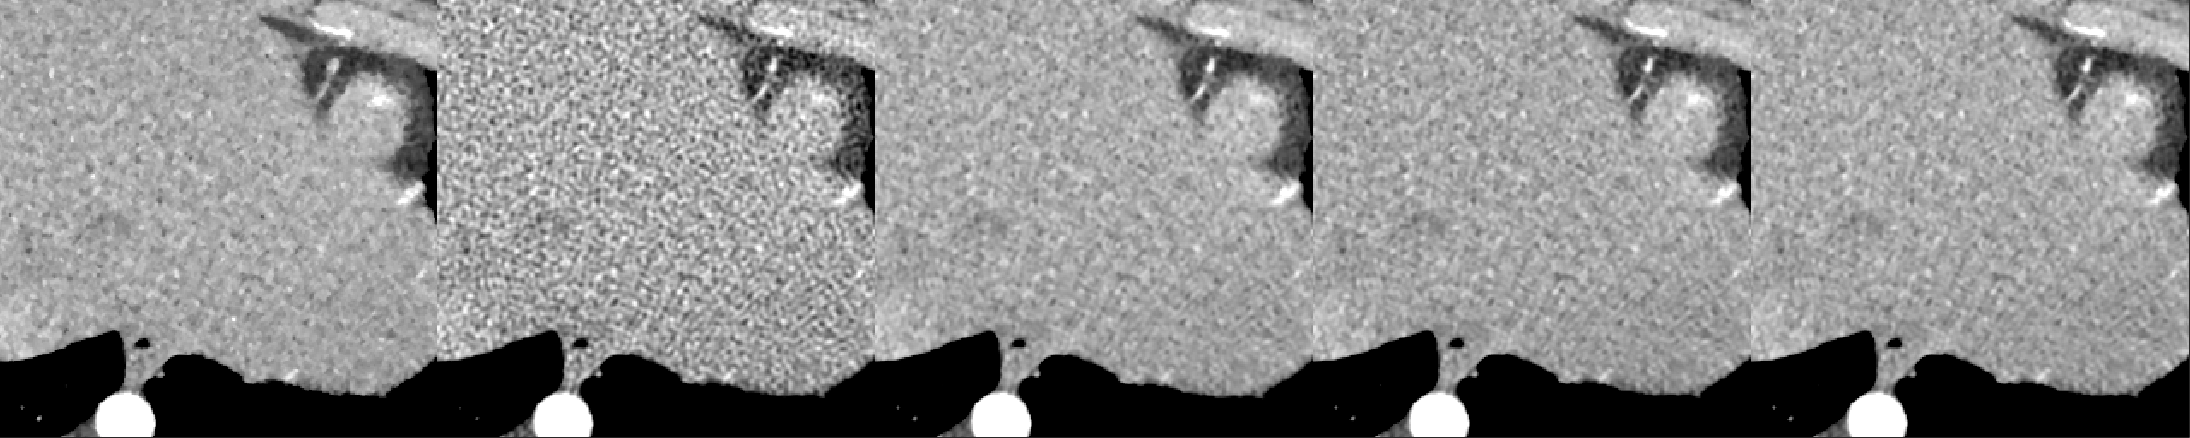

A cardiac FBP image was inferenced on the trained DL-MBIR network. Inference time for every network was between 4 and 6 seconds, and it goes up with the increase in the number of input channels. The MBIR version of the same exam was also available. Figure 3 shows a comparison, for 4 slices – LABEL:sub@fig:Image_10, LABEL:sub@fig:Image_50, LABEL:sub@fig:Image_90, and LABEL:sub@fig:Image_170 in the image volume, among MBIR image, FBP image, and the outputs of DL-MBIRZ𝐷𝐿-𝑀𝐵𝐼subscript𝑅𝑍DL\text{-}MBIR_{Z}, where Z=1, 3, 5𝑍135Z=1,\ 3,\ 5. Figure 4 shows a comparison, for the same slices in the image volume, among difference between images and the MBIR images. Figure 5 has a profile plot to show the comparison of DL-MBIRZ𝐷𝐿-𝑀𝐵𝐼subscript𝑅𝑍DL\text{-}MBIR_{Z} and FBP images w.r.t the MBIR images.

Figure 4: Difference image w.r.t. MBIR. (left to right): FBP𝐹𝐵𝑃FBP, DL-MBIR1𝐷𝐿-𝑀𝐵𝐼subscript𝑅1DL\text{-}MBIR_{1}, DL-MBIR3𝐷𝐿-𝑀𝐵𝐼subscript𝑅3DL\text{-}MBIR_{3}, DL-MBIR5𝐷𝐿-𝑀𝐵𝐼subscript𝑅5DL\text{-}MBIR_{5}. LABEL:sub@fig:Error_10, LABEL:sub@fig:Error_50, LABEL:sub@fig:Error_90 and LABEL:sub@fig:Error_170 represent different slices in the image volume. WW/WL 150/0 HU.

Visually, all DL-MBIR images bear close resemblance to the MBIR images in figure 3. It is confirmed by the difference images in figure 4. In the profile plot of Figure 5, the DL-MBIR profiles closely follow that of MBIR.